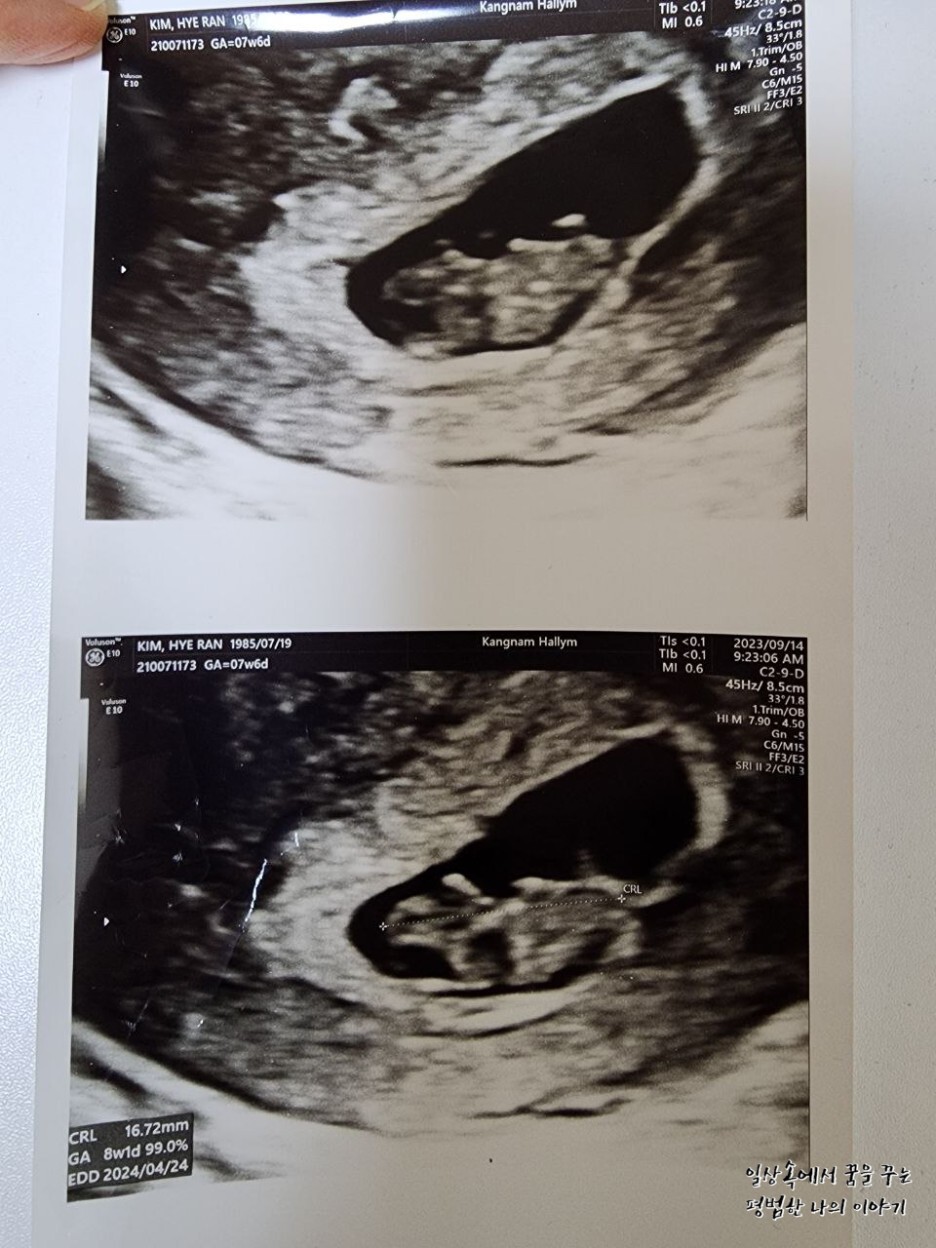

일주일 만에 다시 만난 레오나는 그 새 무럭무럭 자라 있었는데 너무나 귀여운 젤리 곰 모양을 하고 있었다.(초음파를 통해 젤리 곰 형태의 귀여운 태아를 볼 수 있는 주차 수는 보통 8~9주이므로 일부러 이때를 맞춰 산부인과에 방문하는 산모도 있다) 얼굴, 손 그리고 발의 형태를 모두 볼 수 있었는데 둘째인데도 여전히 내 뱃속에서 생명체가 자라고 있다는 사실은 늘 신기하다. 그리고 매번 산부인과에 방문해 성장해 있는 모습을 볼 때마다 감탄한다. 아무래도 첫째 육아를 하면서 임신 과정을 겪는 거라 첫째 임신 때보다 덜 조심하게 되고 덜 신경 쓰게 되고 산부인과도 덜 가게 돼서 항상 미안한 마음이 든다.

레오나의 CRL(=Crown-Rump Length, 태아의 머리부터 엉덩이까지의 길이)은 16.72mm로 평균보다 살짝 컸지만 원래 낳기 전까지 크기는 계속 변하기 때문에 크게 의미를 두지 않아도 될 것 같다.

EDD(Expected Date of Delivery, 출산 예정일)는 보통 12주 전후에 결정되는 날짜가 의미를 가진다. 물론 출산 예정일에 출산을 하는 경우는 드물지만 보통 그 날짜를 바탕으로 출산 계획을 짜면 되더라. 나는 첫째를 40주 차에 유도 분만으로 낳았기 때문에 이번에도 왠지 그럴 것 같은 기분이...